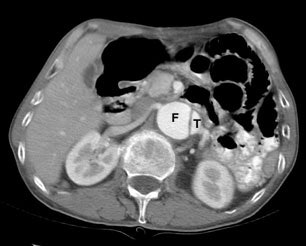

The "beak sign" is demonstrated by the image on the left. In this acute dissection small beaks of contrast (black arrows) extend from the false lumen (F) around the margins of the true lumen (T). The false lumen (F) is also commonly larger than the true lumen (T). |